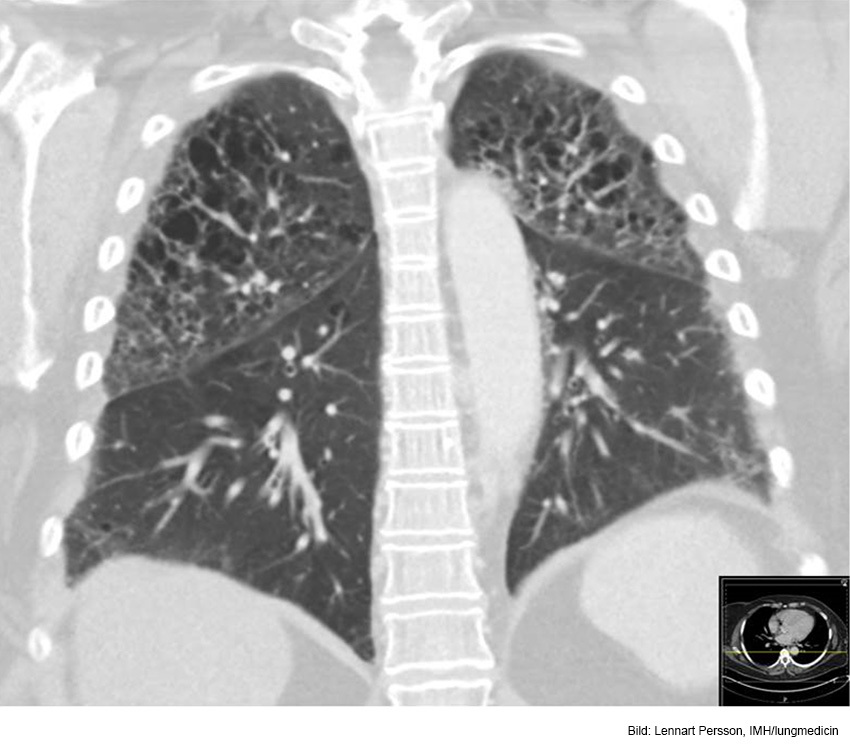

Vad ser du här?

Uttalat emfysem inom bägge ovanlober. Basalt ventralt i höger lunga finns en liten tumörmisstänkt förändring.